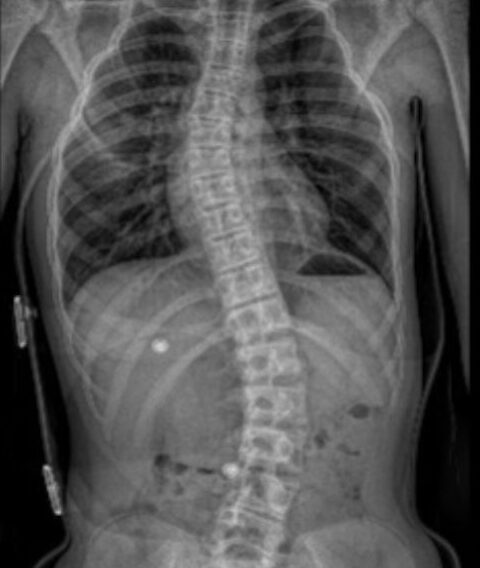

Skolioza to trójpłaszczyznowe skrzywienie kręgosłupa, które najczęściej pojawia się w wieku dziecięcym lub młodzieńczym. Kręgosłup wygina się nie tylko na boki (w płaszczyźnie czołowej), ale też rotuje wokół własnej osi (płaszczyzna poprzeczna) i może zmieniać swoją krzywiznę w płaszczyźnie strzałkowej (np. pogłębiając kifozę lub spłaszczając lordozę). To rotacja kręgów sprawia, że skolioza to nie tylko „krzywe plecy”, ale złożone zaburzenie postawy.

Według definicji medycznej, skolioza to skrzywienie boczne kręgosłupa przekraczające 10 stopni w pomiarze kąta Cobba. Potocznie skoliozą nazywa się każde skrzywienie kręgosłupa, choć nie wszystkie wymagają leczenia. Warto to rozróżniać, by niepotrzebnie nie diagnozować dzieci.